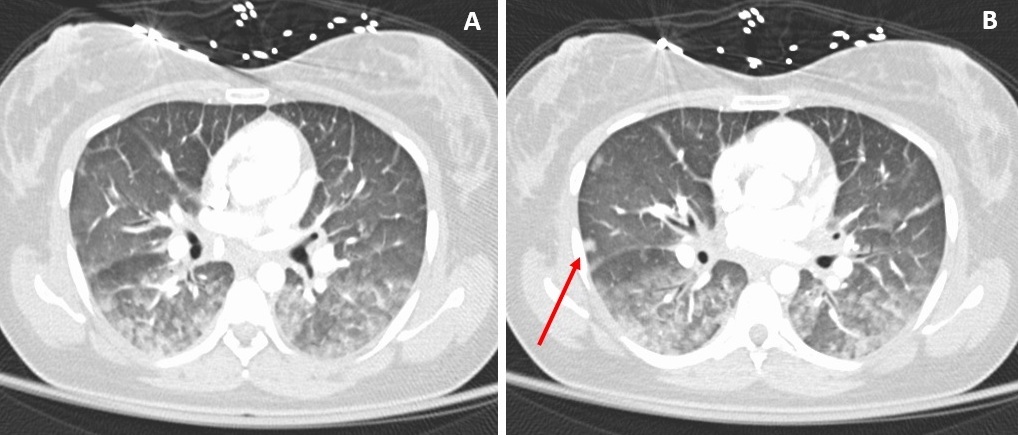

A 36-year-old man presented for evaluation of relapsing fevers. He reported fevers as high as 40 °C and has had 6 such episodes in the past 6 months that have lasted between 2 to 14 days.